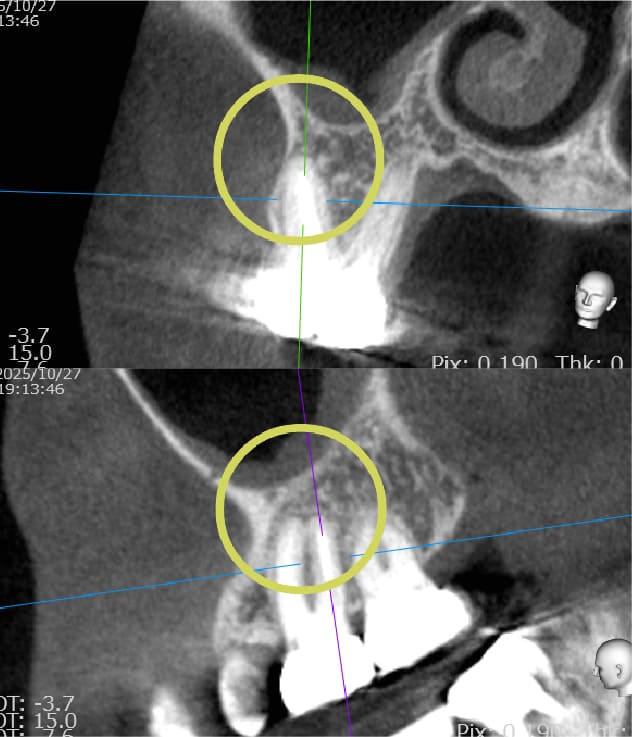

| 歯科用CTによる三次元診断 | 拡大ルーペの使用 |

| 一般的なレントゲン(二次元)では見えない、歯根の複雑な構造や病巣の位置を立体的に正確に把握し、治療の見落としを防ぎます。 | 肉眼では困難な根管内の細部を約8倍に拡大して確認し、処置の精度を高めます。 |

| 歯科用CTによる三次元診断 |

| 一般的なレントゲン(二次元)では見えない、歯根の複雑な構造や病巣の位置を立体的に正確に把握し、治療の見落としを防ぎます。 |